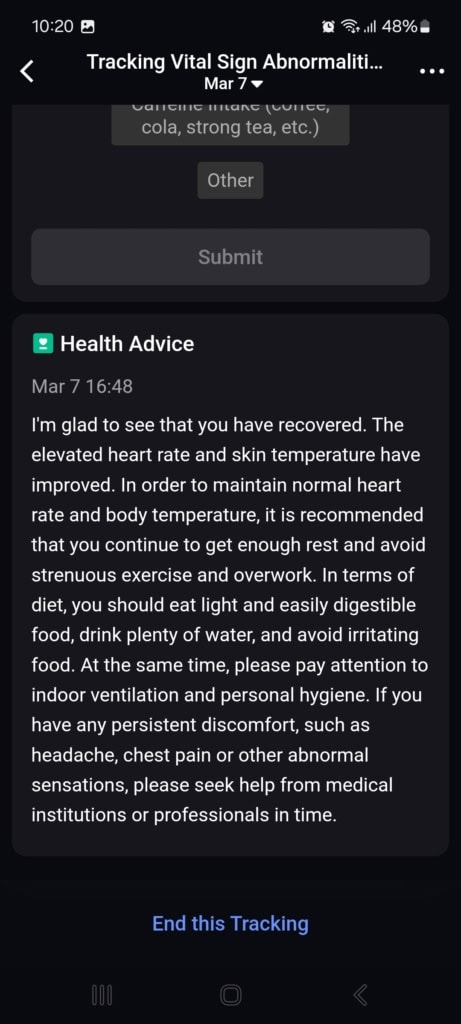

Stan funkcji życiowych (Znaki życia)

W tej części aplikacji dowiesz się o całodziennych wahaniach tętna i jego zmienności, nasyceniu krwi tlenem, częstotliwości oddechów podczas snu i temperaturze snu. Aplikacja porównuje wszystkie te dane z twoją własną referencją z ostatnich 7 do 30 dni oraz z referencyjnymi wartościami medycznymi. Gdy tylko w ciągu dnia lub nocy osiągniesz wartości, które nie mieszczą się w referencyjnych granicach, aplikacja cię o tym poinformuje.

Najczęściej spotykałem się z wyraźnym spadkiem zmienności tętna i wzrostem samego tętna. Te wahania pojawiały się czasem podczas snu, aktywności sportowej lub w przypadkowych sytuacjach, o których nie miałem pojęcia. Mimo że doceniam ten kompleksowy wgląd w moje funkcje życiowe, brakowało mi podczas testowania kontekstu. Funkcja oferuje jedynie wartości i spostrzeżenia, że coś jest nie tak. Nie znalazłem w aplikacji żadnych wskazówek dotyczących możliwych przyczyn ani rekomendacji działań, które mogłyby pomóc przywrócić stan do normy.

Mimo że nietypowe wartości nie mają jasnego kontekstu, aplikacja zwraca na nie uwagę i pyta, co mogło być ich przyczyną (spożycie alkoholu, infekcja, kofeina i inne). W moim przypadku działało to idealnie. Popełniłem błąd dietetyczny, przez który dostałem gorączki i problemów trawiennych. Mój ogólny stan znacznie się pogorszył, co objawiło się wyraźnym spadkiem jakości snu, obniżoną zmiennością tętna i podwyższoną temperaturą ciała. Wszystkie te zmiany zostały przez pierścień i aplikację trafnie rozpoznane i ocenione. Po kilku dniach mój stan się poprawił – również to zostało odnotowane i odpowiednio skomentowane.